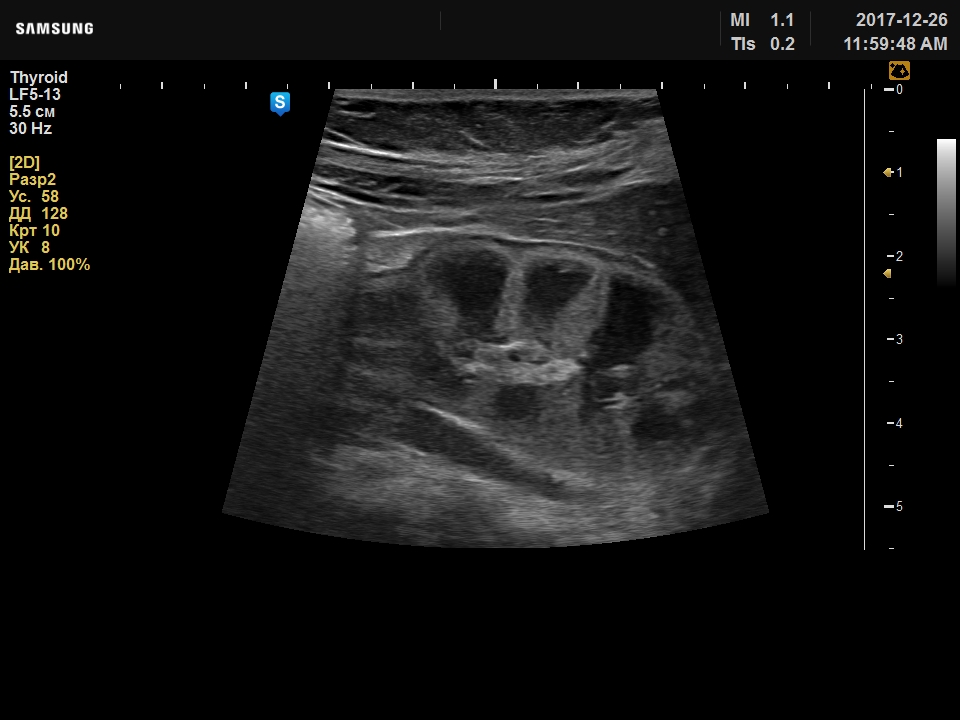

Прошу совета, ребенку 3мес, изменения выявлены около месяца назад в стационаре, где находились по причине желтухи. Вчера были на исследовании у меня: почки нормальных размеров (50х26мм), ЧЛС не расширена, паренхима 11мм, но бросается необычная структура паренхимы, корковый слой повышенной плотности истончен, преобладает мозговой слой в виде больших пирамид, кисты в них не дифференцирую.

Предполагаю дисплазию.

Ваши мысли?

по мне так уз-норма.

Мало вижу почек у детей, но картина у новорожденных отличается от почек детей по-старше. У меня впечатление, что они так и должны выглядеть - фетальная дольчатость, измененное соотношение коркового и мозгового вещества.